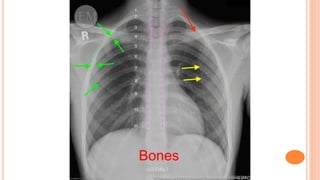

B Bones and soft tissues

Assess the bones visible in the image from top to bottom. The edges of the bones

should be smooth, otherwise a fracture may be indicated. Also assess for bone

density, oedema or metastatic lesion.

Bones